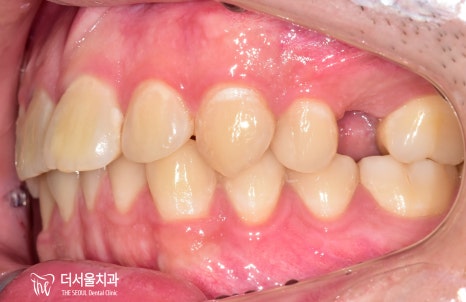

교합면을보면 뭔가 좁다는 느낌을 받을 수 있는데,

치아를 상실한지 조금 오래 되었다 하셨습니다.

그래서 25번 위치는 픽스처를 식립하기

힘든 상태였습니다.

따라서 성남 치아교정 치료를

먼저 진행하여 공간을 만들기로 합니다.